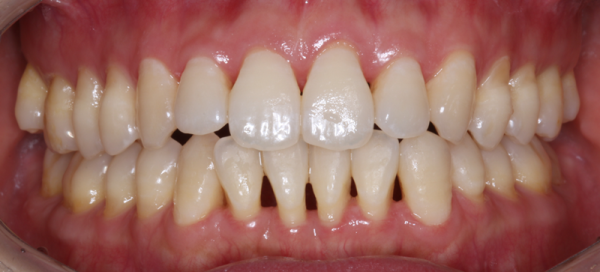

치료 전과 치료 후는 이렇게 달라집니다.